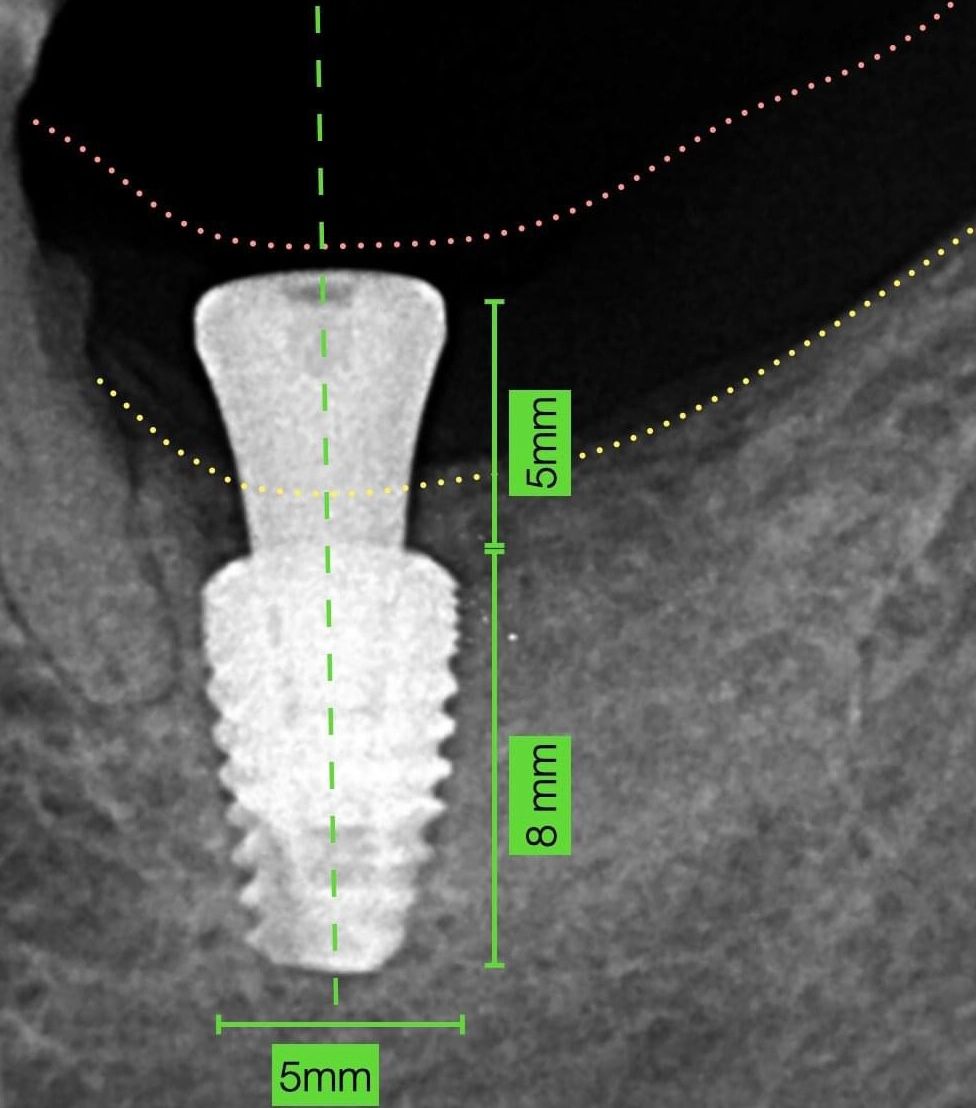

Le recomendamos realizar un estudio mas extenso llamado cone beam para ver el grado de afectación, le sugerimos acudir a una consulta para valorar su caso. Quedamos a sus órdenes.